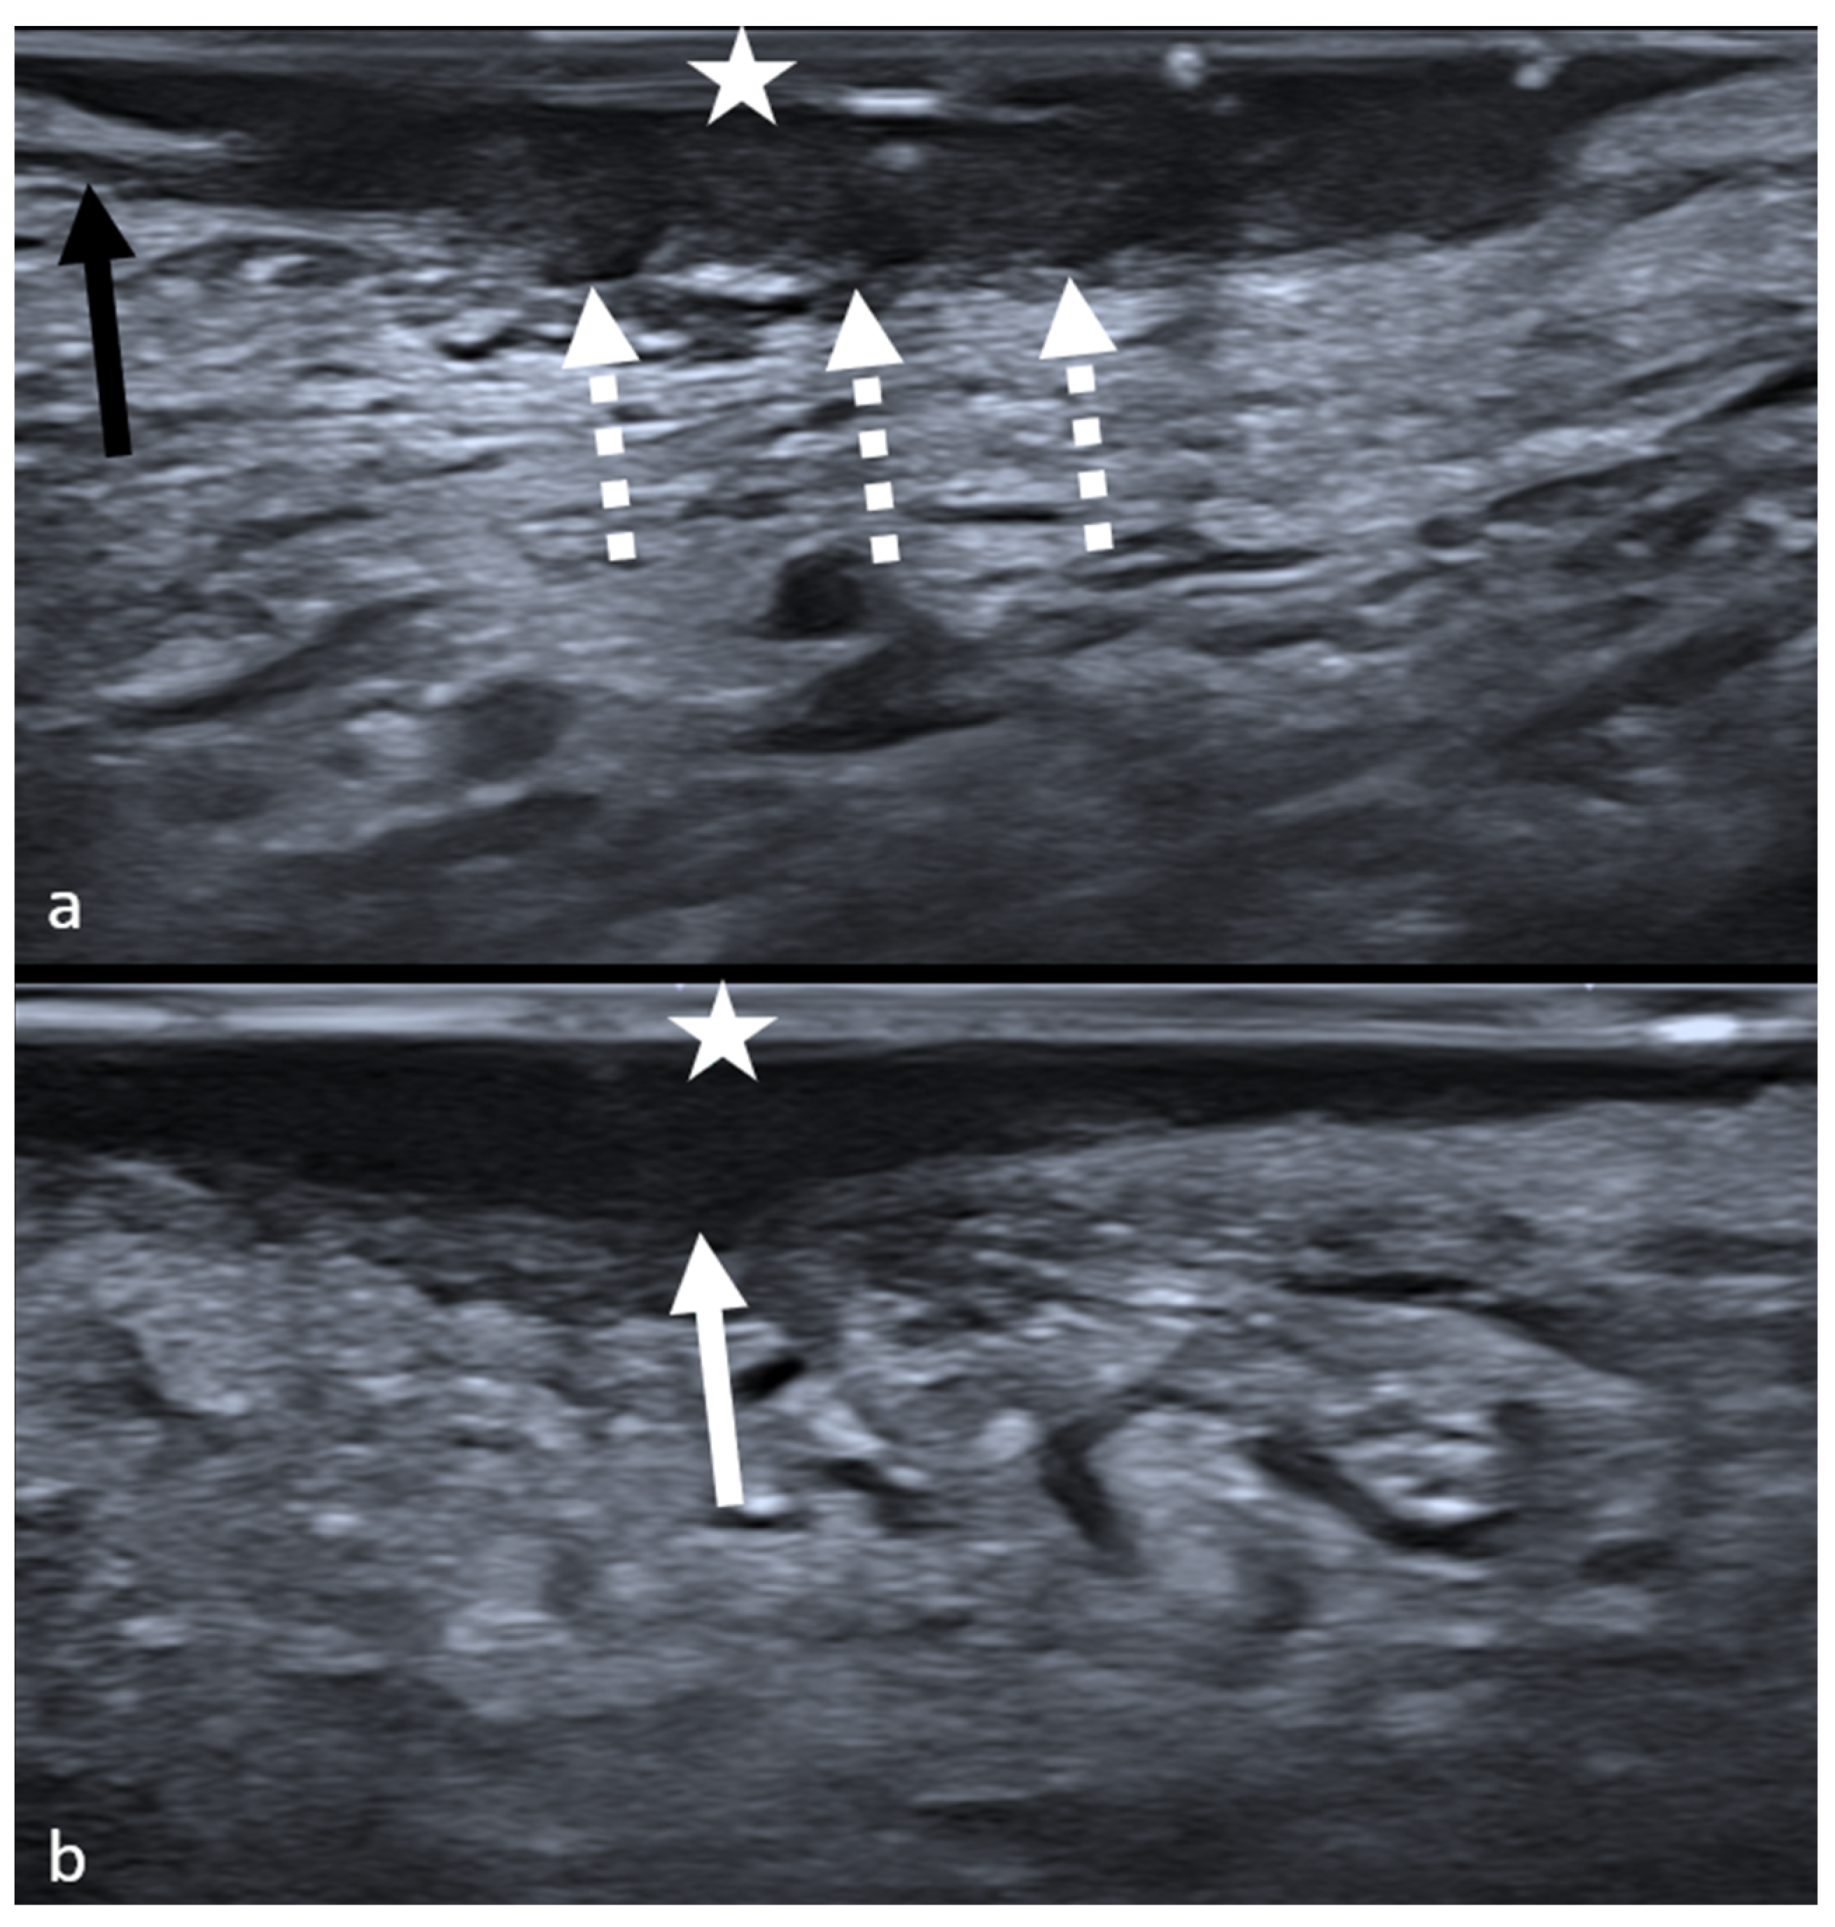

2.2. Intraoral Ultrasound and Image Examination